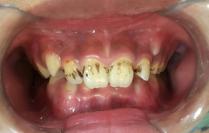

8岁孩子口内外源性染色

牙齿分为内源性和外源性,今天着重介绍外源性染色。外源性牙齿染色的原因很多,总结起来有以下的原因:日常饮食黑色素较多的食物(最常见),长期服用颜色较深的中药,口腔内产黑色素细菌活跃等。染色一般位于牙齿的唇颊侧,部分严重的患儿可有舌侧及咬合面的染色。